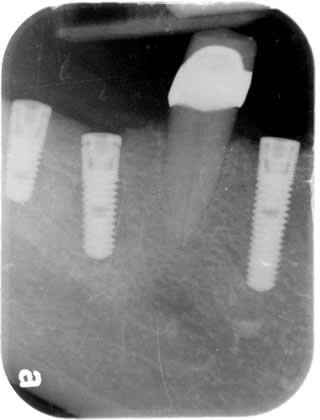

3 Implants:

Feb 2009

Going to wait four months after the implants are placed before the crowns can be placed.